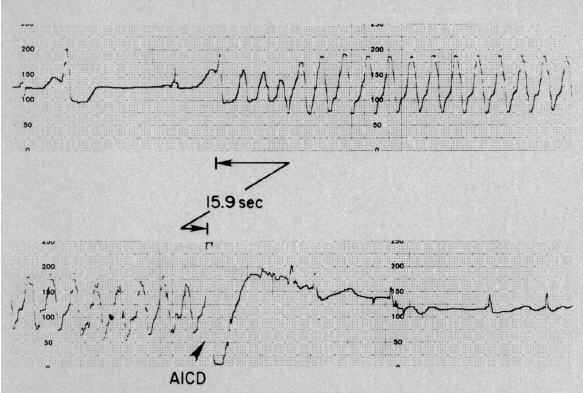

1980年8月7日

一篇报道最早描述了使用植入式自动除颤器治疗顽固性药物治疗不敏感的室性心律失常。现在这被称为"植入式心律复律器和除颤仪"(ICD),它可以识别并逆转潜在的室性心律失常,如今ICD已经成为了治疗致死性心律失常的重要选择。